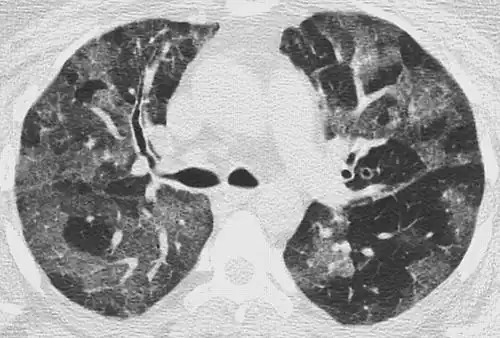

CT image showing crazy paving pattern of ground-glass opacities in both lungs.

The crazy paving pattern may occur when there is both interlobular and intralobular widening. This sometimes resembles a road paved with irregular bricks or tiles. It is typically diffuse, involving larger areas of one or multiple lobes. There are a variety of potential causes, including Pneumocystis pneumonia, late-stage adenocarcinoma, pulmonary edema, some types of idiopathic interstitial pneumonias, diffuse alveolar hemorrhage, sarcoidosis, and pulmonary alveolar proteinosis.[6] COVID-19 has also been shown to occasionally cause GGOs with a crazy paving pattern.[11]